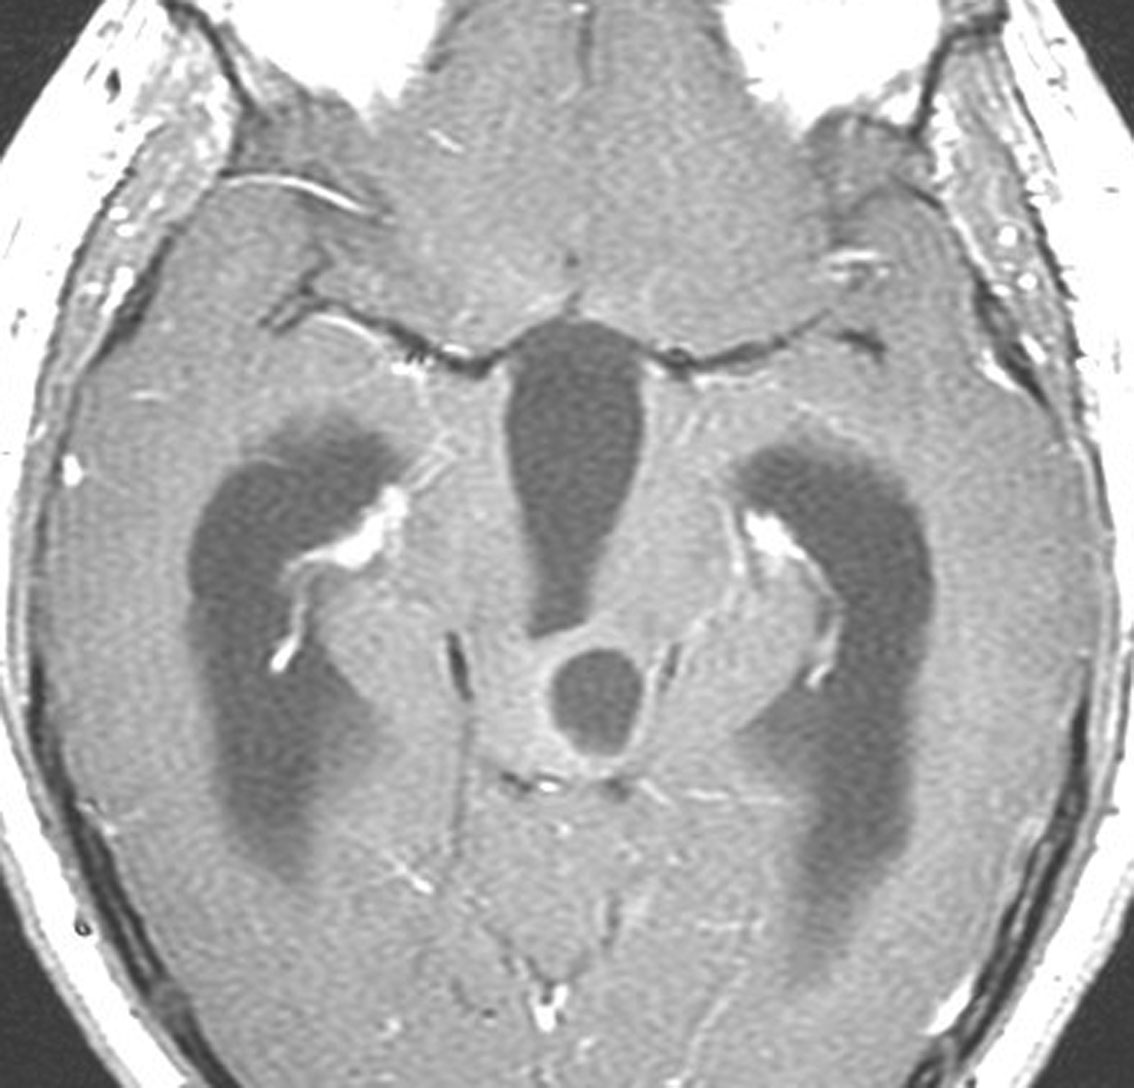

tectal gliomaに間違えそうなPPTID 松果体実質腫瘍

上段のガドリニウム増強MRIでは松果体腫瘍に見えやや境界が不明瞭なので,年齢からはPPTIDが疑われます。しかし,CISSの画像で,中脳上丘との境界がなく中脳腫大があるようにみえ,テクタールグリオーマを疑って経過観察しました。腫瘍がゆっくり増大したので摘出したところPPTIDという診断がつきました。